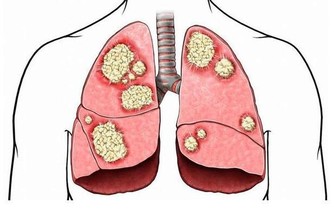

2、健康隱患。生病也是會導致噩夢的,如果長時間做同一個噩夢,夢到我們身體的某個部位,那可以預示著這個部位可能有問題,自己要多去注意。